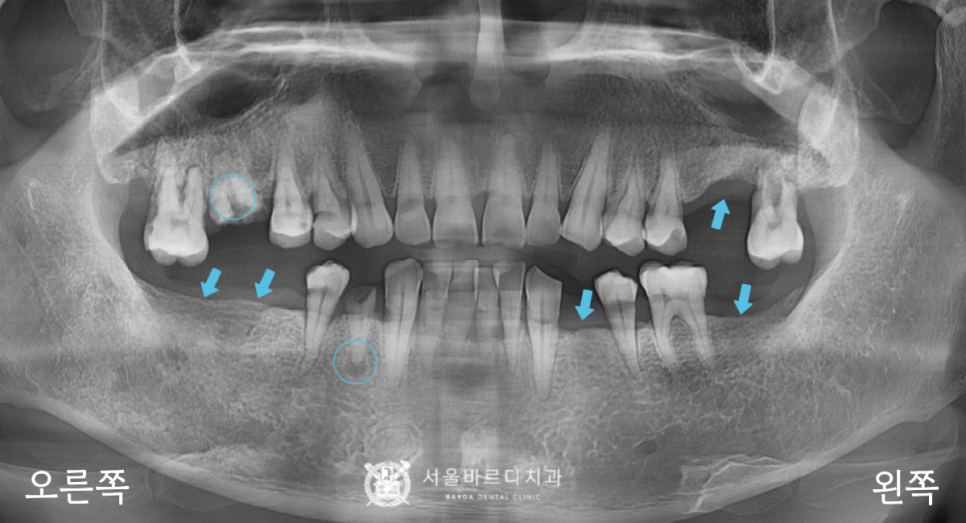

전반적인 뼈와 치아 상태를 확인하는

파노라마 엑스레이를 촬영하여 보니

기존에 이를 뽑은 자리가 많이 있었고,

오른쪽 위아래에 뿌리만 남은 부위가 있었습니다.